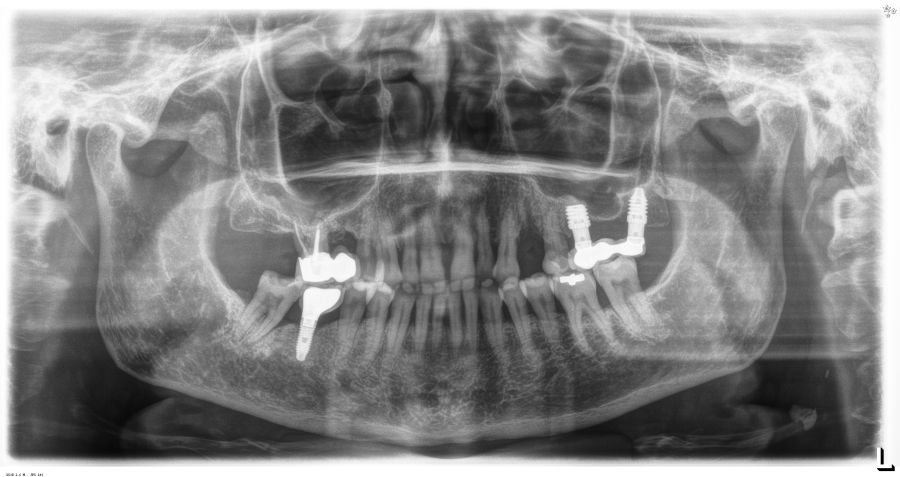

En cuanto a la rehabilitación protésica, en todos los casos se utilizó una prótesis atornillada con transepitelial para prótesis unitaria. La supervivencia de las prótesis fue del 100%, sin encontrarse fracaso en ninguna de ellas al igual que los implantes, con un tiempo de seguimiento de tres años. Durante el primer año, en las visitas de control, ninguno de los implantes mostró sangrado al sondaje ni inflamación de los tejidos periimplantarios. La media de la pérdida ósea en este punto fue de 0,32 mm (+/- 0,60) y la media de la pérdida ósea distal de 0,31 (+/- 0,48). A los dos años, no se registraron tampoco signos inflamatorios en ninguno de los implantes y la pérdida ósea mesial del conjunto fue de media de 0,38 mm (+- 0,54) y la distal de 0,64 mm (+/- 0,70). En la última visita a los 3 años, los tejidos periimplantarios siguieron estables, sin signos de inflamación y la media de la pérdida ósea mesial fue de 0,40 mm (+/- 0,53) y la distal de 0,69 (+/- 0,55) (Figura 5). En las Figuras 6-12 se muestra uno de los casos incluidos en el estudio.